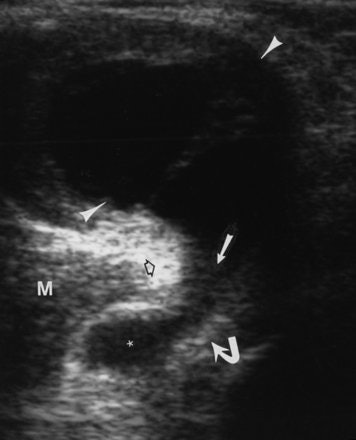

![]() |

| A 60-year-old woman with Baker's cyst. Axial sonogram of posterior knee shows Baker's cyst (arrowheads) with fluid (solid straight arrow) between semimembranosus tendon (curved arrow) and medial gastrocnemius (open arrow). Note subgastrocnemius component (asterisk) of Baker's cyst. Note that top of image is posterior; right side of image is medial. M = medial gastrocnemius muscle. Ward EE, Jacobson JA, Fessell DP, Hayes CW, and van Holsbeeck M, "Sonographic Detection of Baker's Cysts Comparison with MR Imaging" (AJR 2001; 176:373-380). |